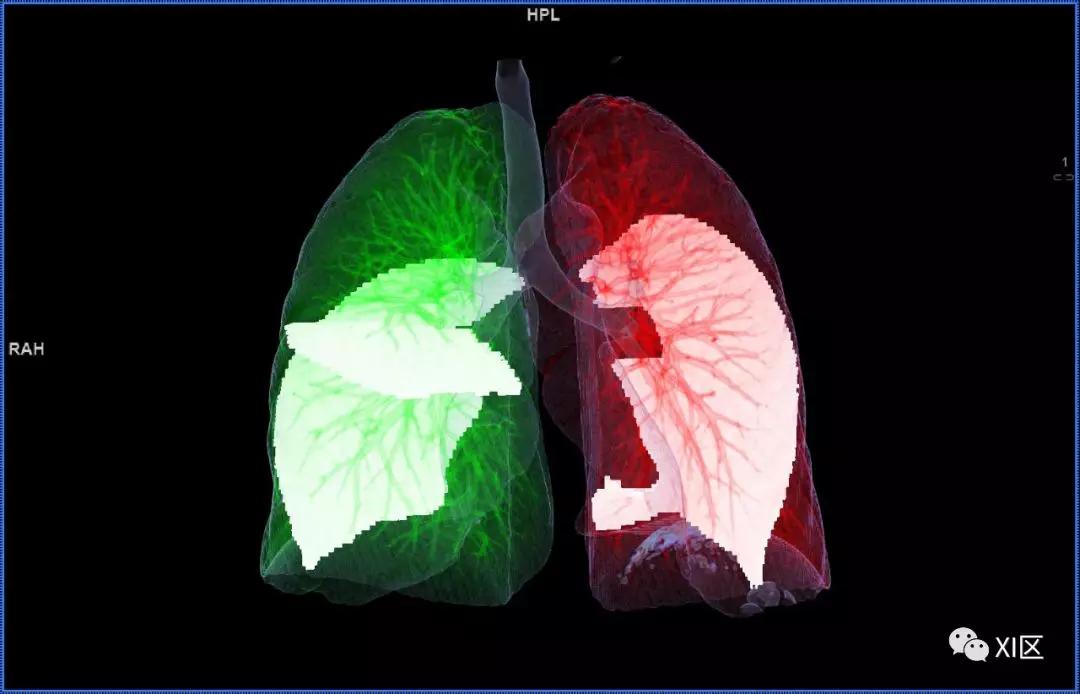

前后位,双侧位,后前位显示气道肺与胸部骨骼的关系

气管支气管树与两肺融合显示

气管树与左右肺的关系